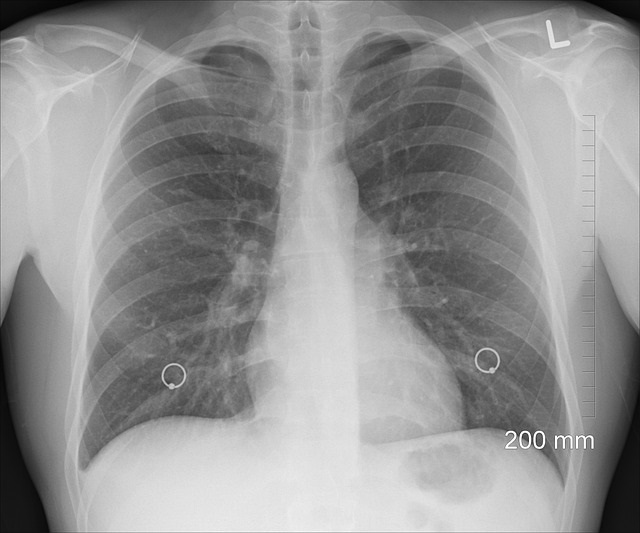

Cancro ai polmoni, screening dopo i 55 anni anche per i non fumatori

Anche i non fumatori dovrebbero sottoporsi a uno screening dopo i 55 anni per scongiurare malattie come il cancro ai polmoni. La proposta arriva dal National Screening Committee (UKNSC) del Regno Unito, che ha chiesto che i controlli vengano implementati in massa anche per chi non ha mai acceso una sigaretta nella sua vita. Più del 70% dei tumori polmonari è causato dal fumo. La dipendenza aumenta anche il rischio per altri 14 tipi di tumore. La raccomandazione è stata supportata da Cancer Research, il cui direttore esecutivo ha chiesto che fosse implementato il controllo “il più rapidamente possibile”.

“Accogliamo con favore questa raccomandazione e sollecitiamo i governi di tutte e quattro le nazioni del Regno Unito a lanciare un programma mirato di screening del cancro ai polmoni il più rapidamente possibile”, ha detto il dottor Ian Walker a The Telegraph. “Il cancro del polmone provoca più decessi nel Regno Unito rispetto a qualsiasi altro tipo di cancro e lo screening potrebbe salvare vite diagnosticando le persone in una fase precoce, quando è più probabile che il trattamento abbia successo”.

Il cancro ai polmoni è uno dei tumori più temuti, ma la ricerca sta facendo progressi per rendere più efficaci le cure. Nuovi studi presentati al congresso della Società europea di oncologia medica (Esmo), che lo scorso settembre ha riunito a Parigi oltre 25mila oncologi da tutto il mondo, hanno proposto innovative terapie mirate, che hanno dimostrato di funzionare sul lungo termine e la sopravvivenza dei pazienti sta aumentando in modo significativo anche per le forme metastatiche o più resistenti. Lo dimostrano una serie di ricerche, accolte con grande entusiasmo dagli esperti che, solo fino a poco tempo fa, avevano pochissime armi terapeutiche contro varie forme di neoplasia polmonare.

La sopravvivenza a lungo termine diventa così realtà per i pazienti colpiti da tumore del polmone metastatico, una delle neoplasie più difficili da trattare. Un risultato ottenuto grazie alla combinazione di pembrolizumab, molecola immunoterapica, con la chemioterapia, che ha evidenziato, nel trattamento di prima linea del tumore del polmone non a piccole cellule (NSCLC) metastatico, un beneficio in sopravvivenza: gli studi dimostrano che un paziente su 5 è infatti vivo a 5 anni. Foto di oracast da Pixabay.